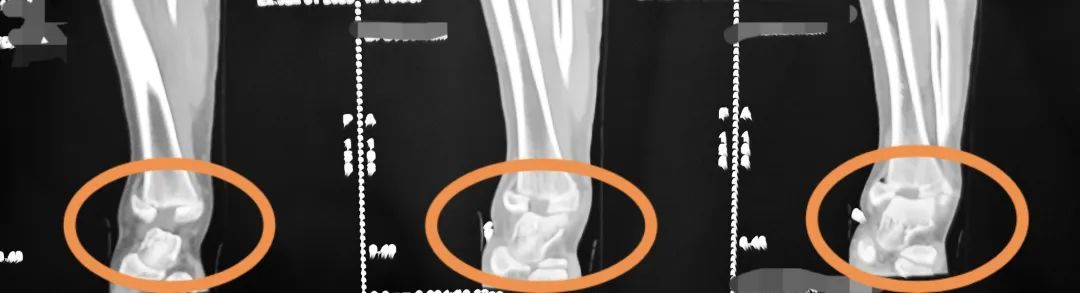

术前侧位图

术前正位图

明确诊断为

右侧胫腓骨远端粉碎性骨折

累及骨骺、关节面